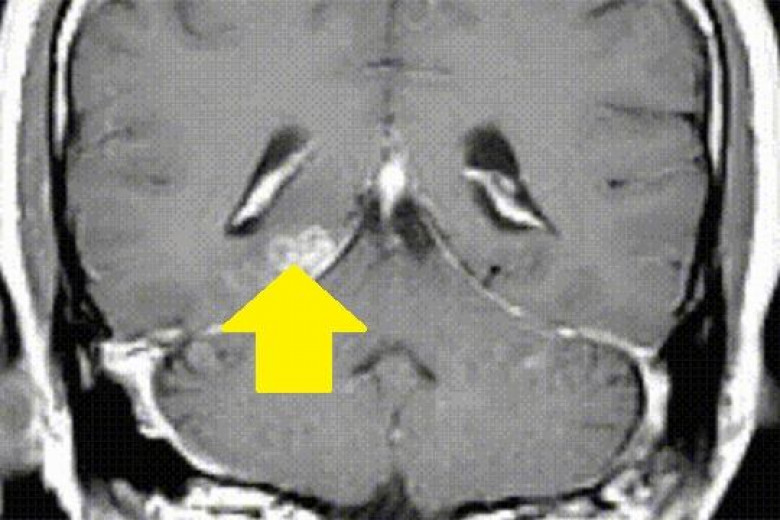

Բրիտանիայում ապրող չինացի տղամարդու մոտ բժիշկները 10 սանտիմետրանոց երիզորդ (Spirometra erinaceieuropaei) են հայտնաբերել, հայտնում է Genome Biology ամսագիրը: Չինացին 2008թ. սկսել է բողոքել գլխացավերից, նոպաներից, հիշողության կորստից և տարօրինակ հոտերի զգացողությունից: Այդ ժամանակ տոմոգրաֆիայից հետո ուղեղի վնասվածք է հայտնաբերվել, իսկ հետո ուղեղի հյուսվածքներում որդ է հայտնաբերվել:

2012թ. բժիշկները որդը հեռացրել են չինացու ուղեղից, սակայն նրա առողջական խնդիրները չեն ավարտվել: Spirometra erinaceieuropaei որդը հանդիպում է Չինաստանում, այն վարակում է երկկենցաղներին և խեցեմորթներին, ուստի բժիշկները ենթադրել են, որ տղամարդը վարակվել է Չինաստան այցերից մեկի ժամանակ, որտեղ պատրաստված գորտ է կերել: